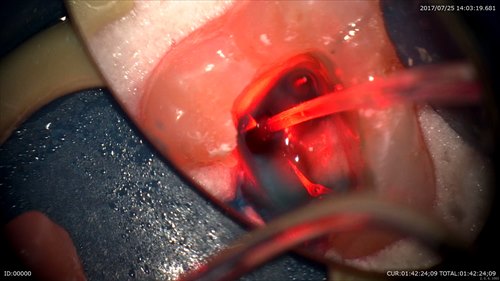

レーザー中も。